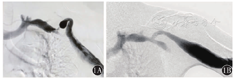

患者 男性,37岁,因"上臂透析通路突发全段红肿热痛,震颤消失1 d"于2017年5月31日入院。查体见上臂头静脉全程红肿膨大,触痛明显,搏动及震颤均消失。患者曾因"肾小球肾炎"致肾功能衰竭,于2000年开始建立左上肢动静脉内瘘(arteriovenous fistula,AVF)进行规律血液透析,其间因通路失功多次进行重建术。曾行左腕部头静脉-桡动脉自体动静脉内瘘、左前臂贵要静脉移位内瘘、左前臂近肘部桡动脉-头静脉AVF及左肘部肱动脉-头静脉自体动静脉内瘘(brachiocephalic fistula,BCF)。自2015年开始(BCF手术后1年)逐渐出现静脉压升高。患者于2017年3月就诊我院,查体见左肘部AVF吻合口可及震颤,上臂头静脉扩张伴迂曲,搏动感强。数字减影血管造影(digital subtraction angiography,DSA)提示左头静脉弓狭窄(cephalic arch stenosis,CAS)(图1A),但患者未遵医嘱及时手术。本次入院诊断为上臂头静脉血栓形成。2017年6月5日在全麻下手术治疗。取左锁骨下横切口,自锁骨下方分离胸大肌并向下牵引,切开胸锁筋膜,显露锁骨下动静脉及头静脉弓汇入部,注意勿伤及胸肩峰动静脉及胸外侧神经。充分游离头静脉弓汇入两端各约1.5 cm长锁骨下静脉并阻断,切除头静脉弓闭塞段(图2A),Fogarty取栓导管取出头静脉内血栓,肝素盐水冲洗管腔后,修剪头静脉弓冗长段并与锁骨下静脉建立端-侧吻合,吻合口约1.0 cm(图2B)。术后内瘘恢复震颤,流量可满足透析要求,于2017年6月12日出院。手术后1个月复查DSA显示吻合口形态良好(图1B)。